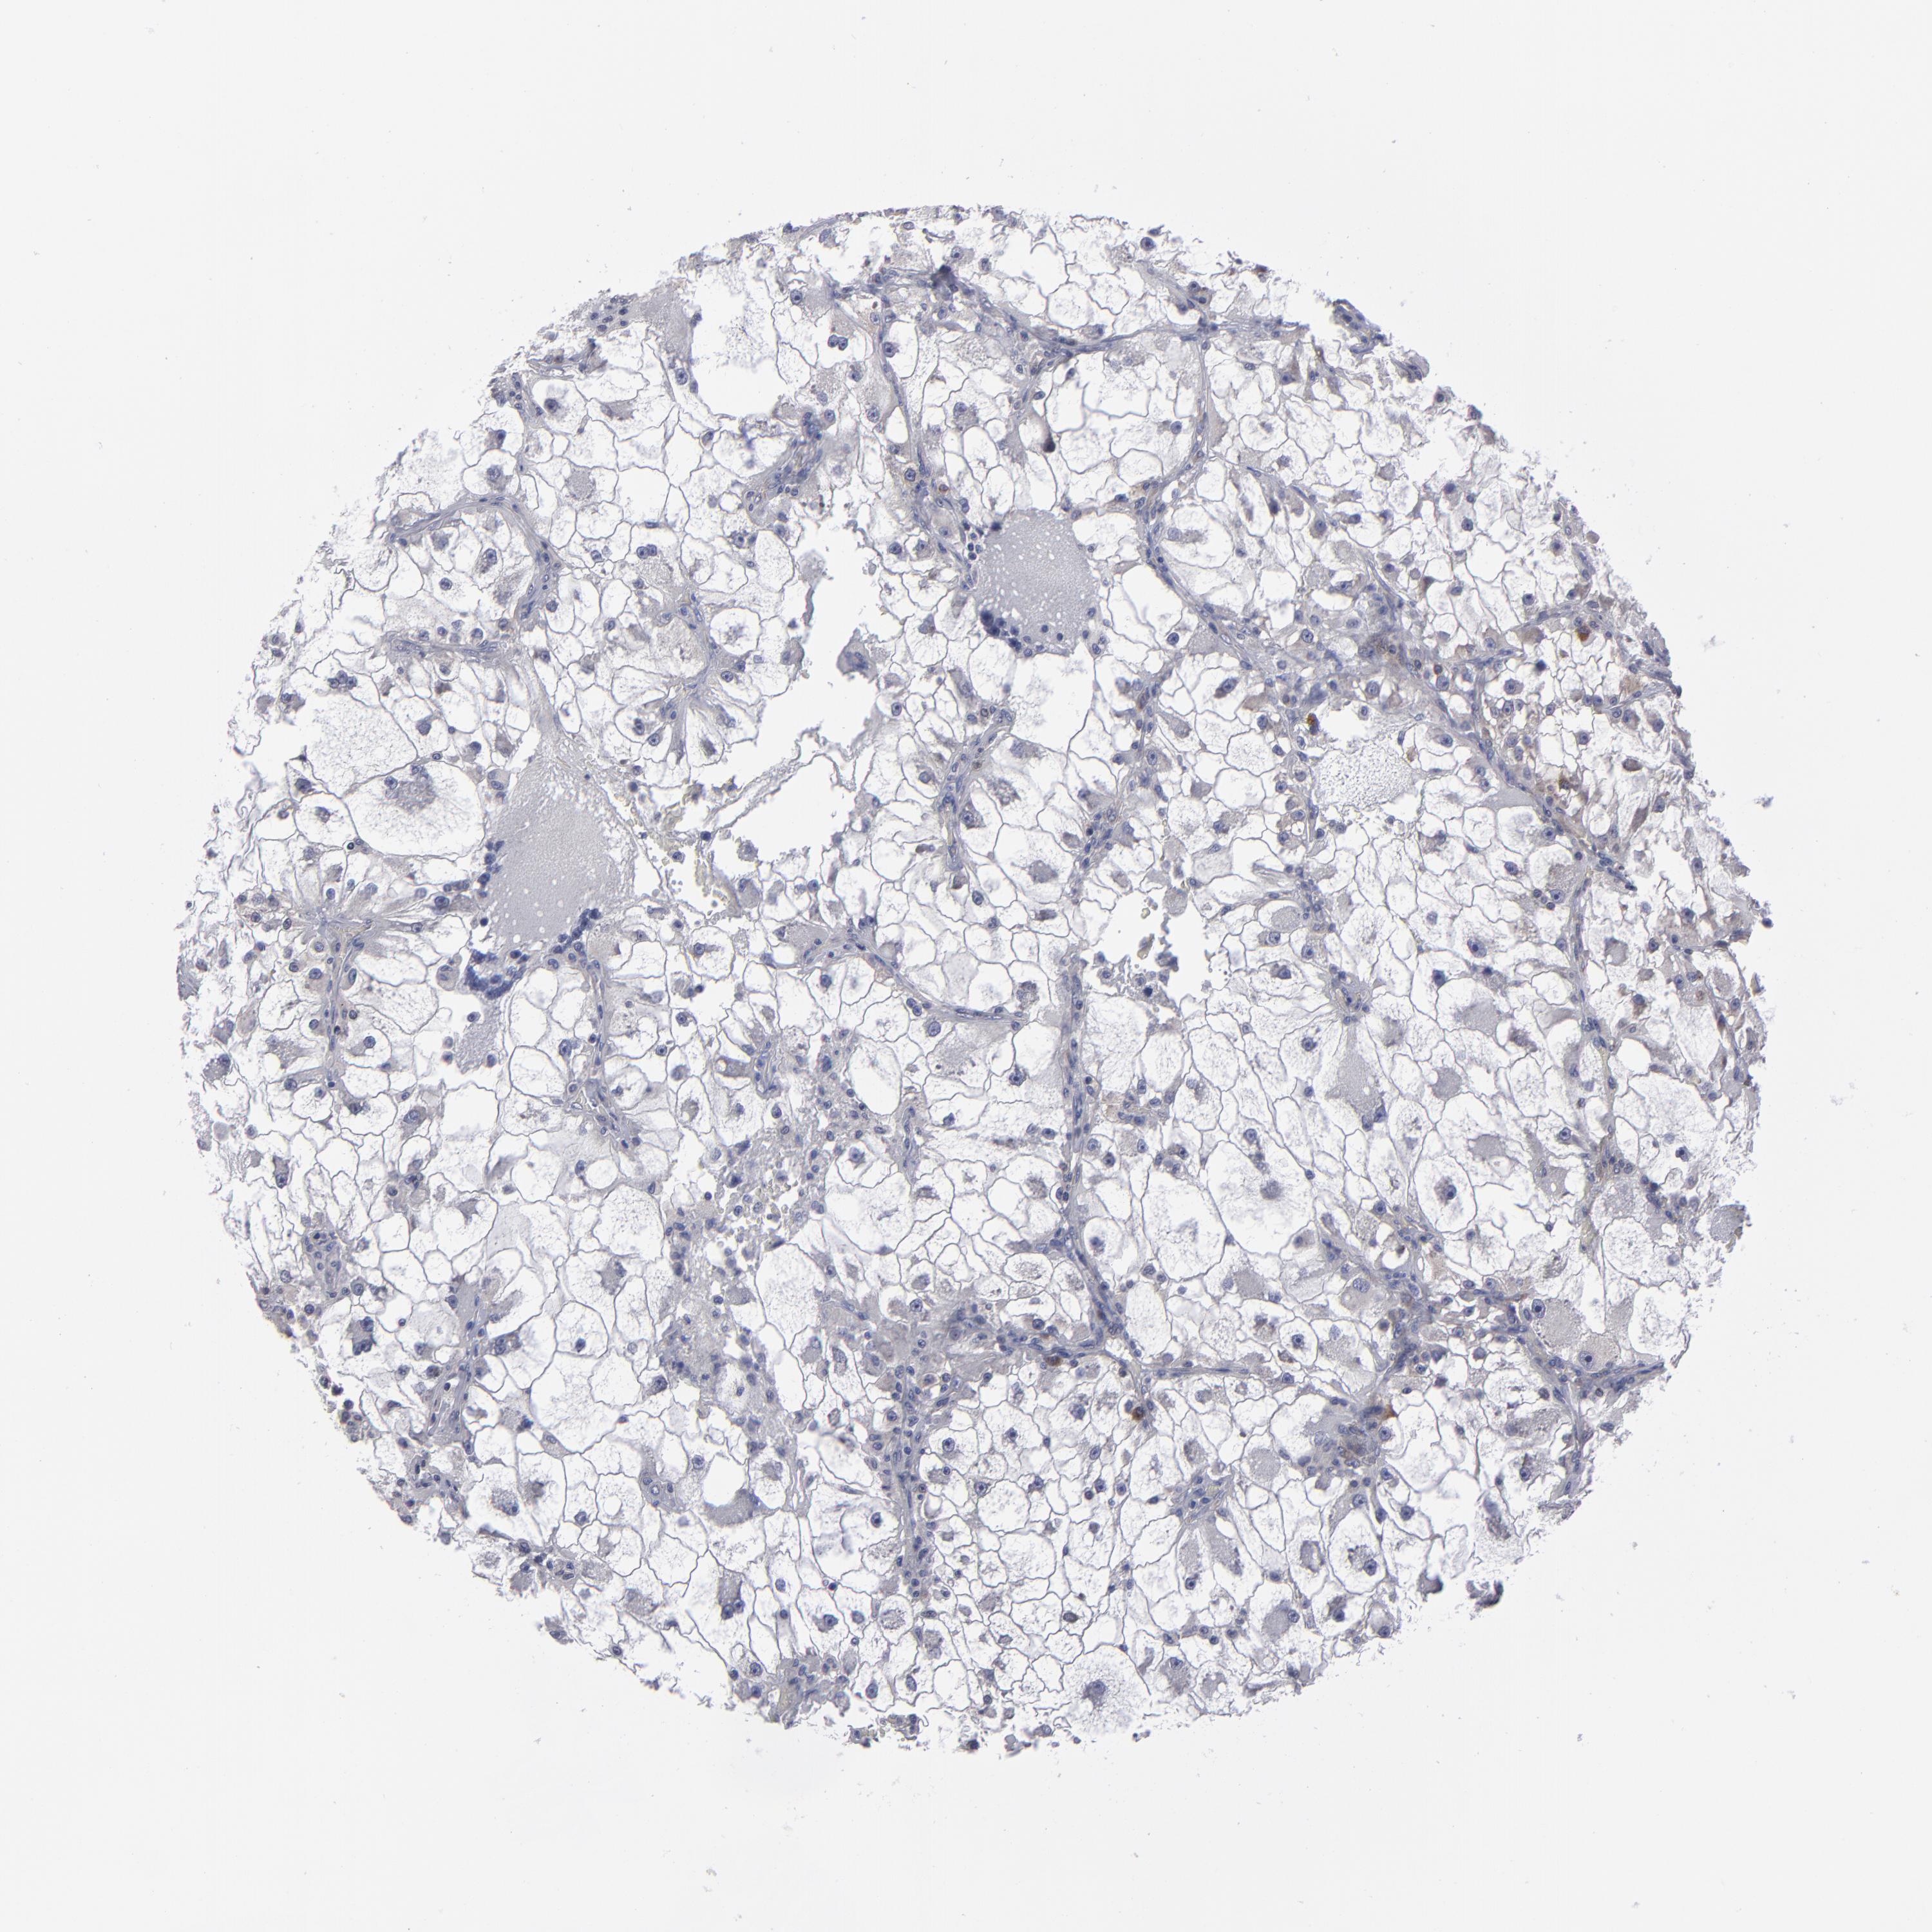

CANCER RENAL CANCER Show tissue menu

KICH TCGA KIRC TCGA KIRC VALIDATION KIRP TCGA PROTEIN RCC CPTAC PROTEIN EXPRESSION